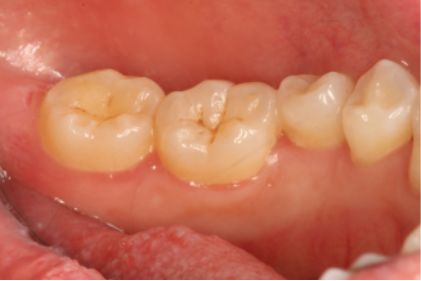

术前

女,38岁,主诉牙龈出血1年,无系统疾病及药物过敏史。检查:牙列式18-27、37-47;18伸长,无咬合;口腔卫生欠佳,可见牙石、软垢,后牙区牙石软垢较多,全口牙龈边缘充血水肿,探诊出血阳性,牙周探诊深度3-4mm。诊断为慢性牙周炎(轻度)。